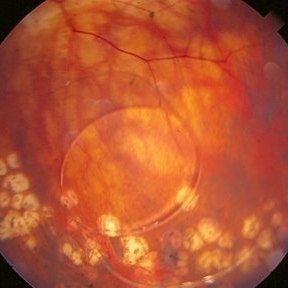

A 4-year-old male patient attended the clinic for evaluation. In the mapping examination and retina and retinography, important alterations were observed in the posterior pole of the left eye. This in turn was sent to perform the ocular ultrasonography examination, which together with the previous examinations, confirmed changes that suggested diagnosis of: COMBINED HAMARTOMA OF RETINA AND PIGMENTARY EPITHELIUM.

Photographer: JEFFERSON R SOUSA - Study Center and Ophthalmological Research Dr. Andre M V Gomes, Institute Dr. Suel Abujamra São Paulo-Brazil

Imaging device: Topcon TRC-50 DX, Imaginet 5.0, angle de 35º . Flash 36 / Mosaic with 9 images.

Condition/keywords: combined hamartoma, retinal pigment epithelium (RPE) hamartoma, tumor